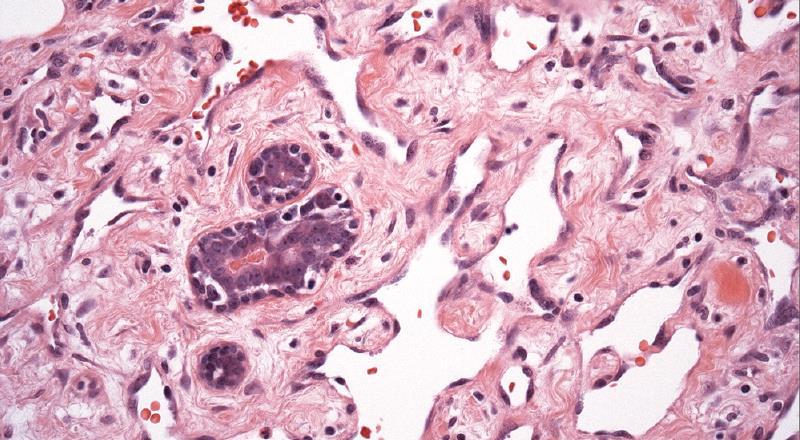

A 43 year old woman, previously treated for invasive ductal carcinoma, presents with a breast lump and blue discolouration of the overlying skin. Biopsy shows a tumour composed of irregular spaces lined by pleomorphic cells, abnormal mitoses and infiltration into the surrounding tissue. The tumour cells are negative for AE1/AE3 and positive for CD31 and CD34.

Overall rare breast tumour Known to be associated with previous radiotherapy Irregular vascular spaces, variably pleomorphic cells. Positive for vascular markers CD31 and CD34 and usually negative for epithelial markers

Atypical vascular proliferation after radiotherapy Other haemangiomas

Low High

High